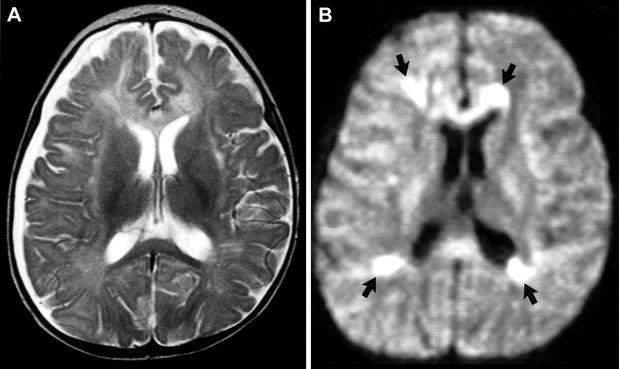

DWI (Difussión weighted imaging)